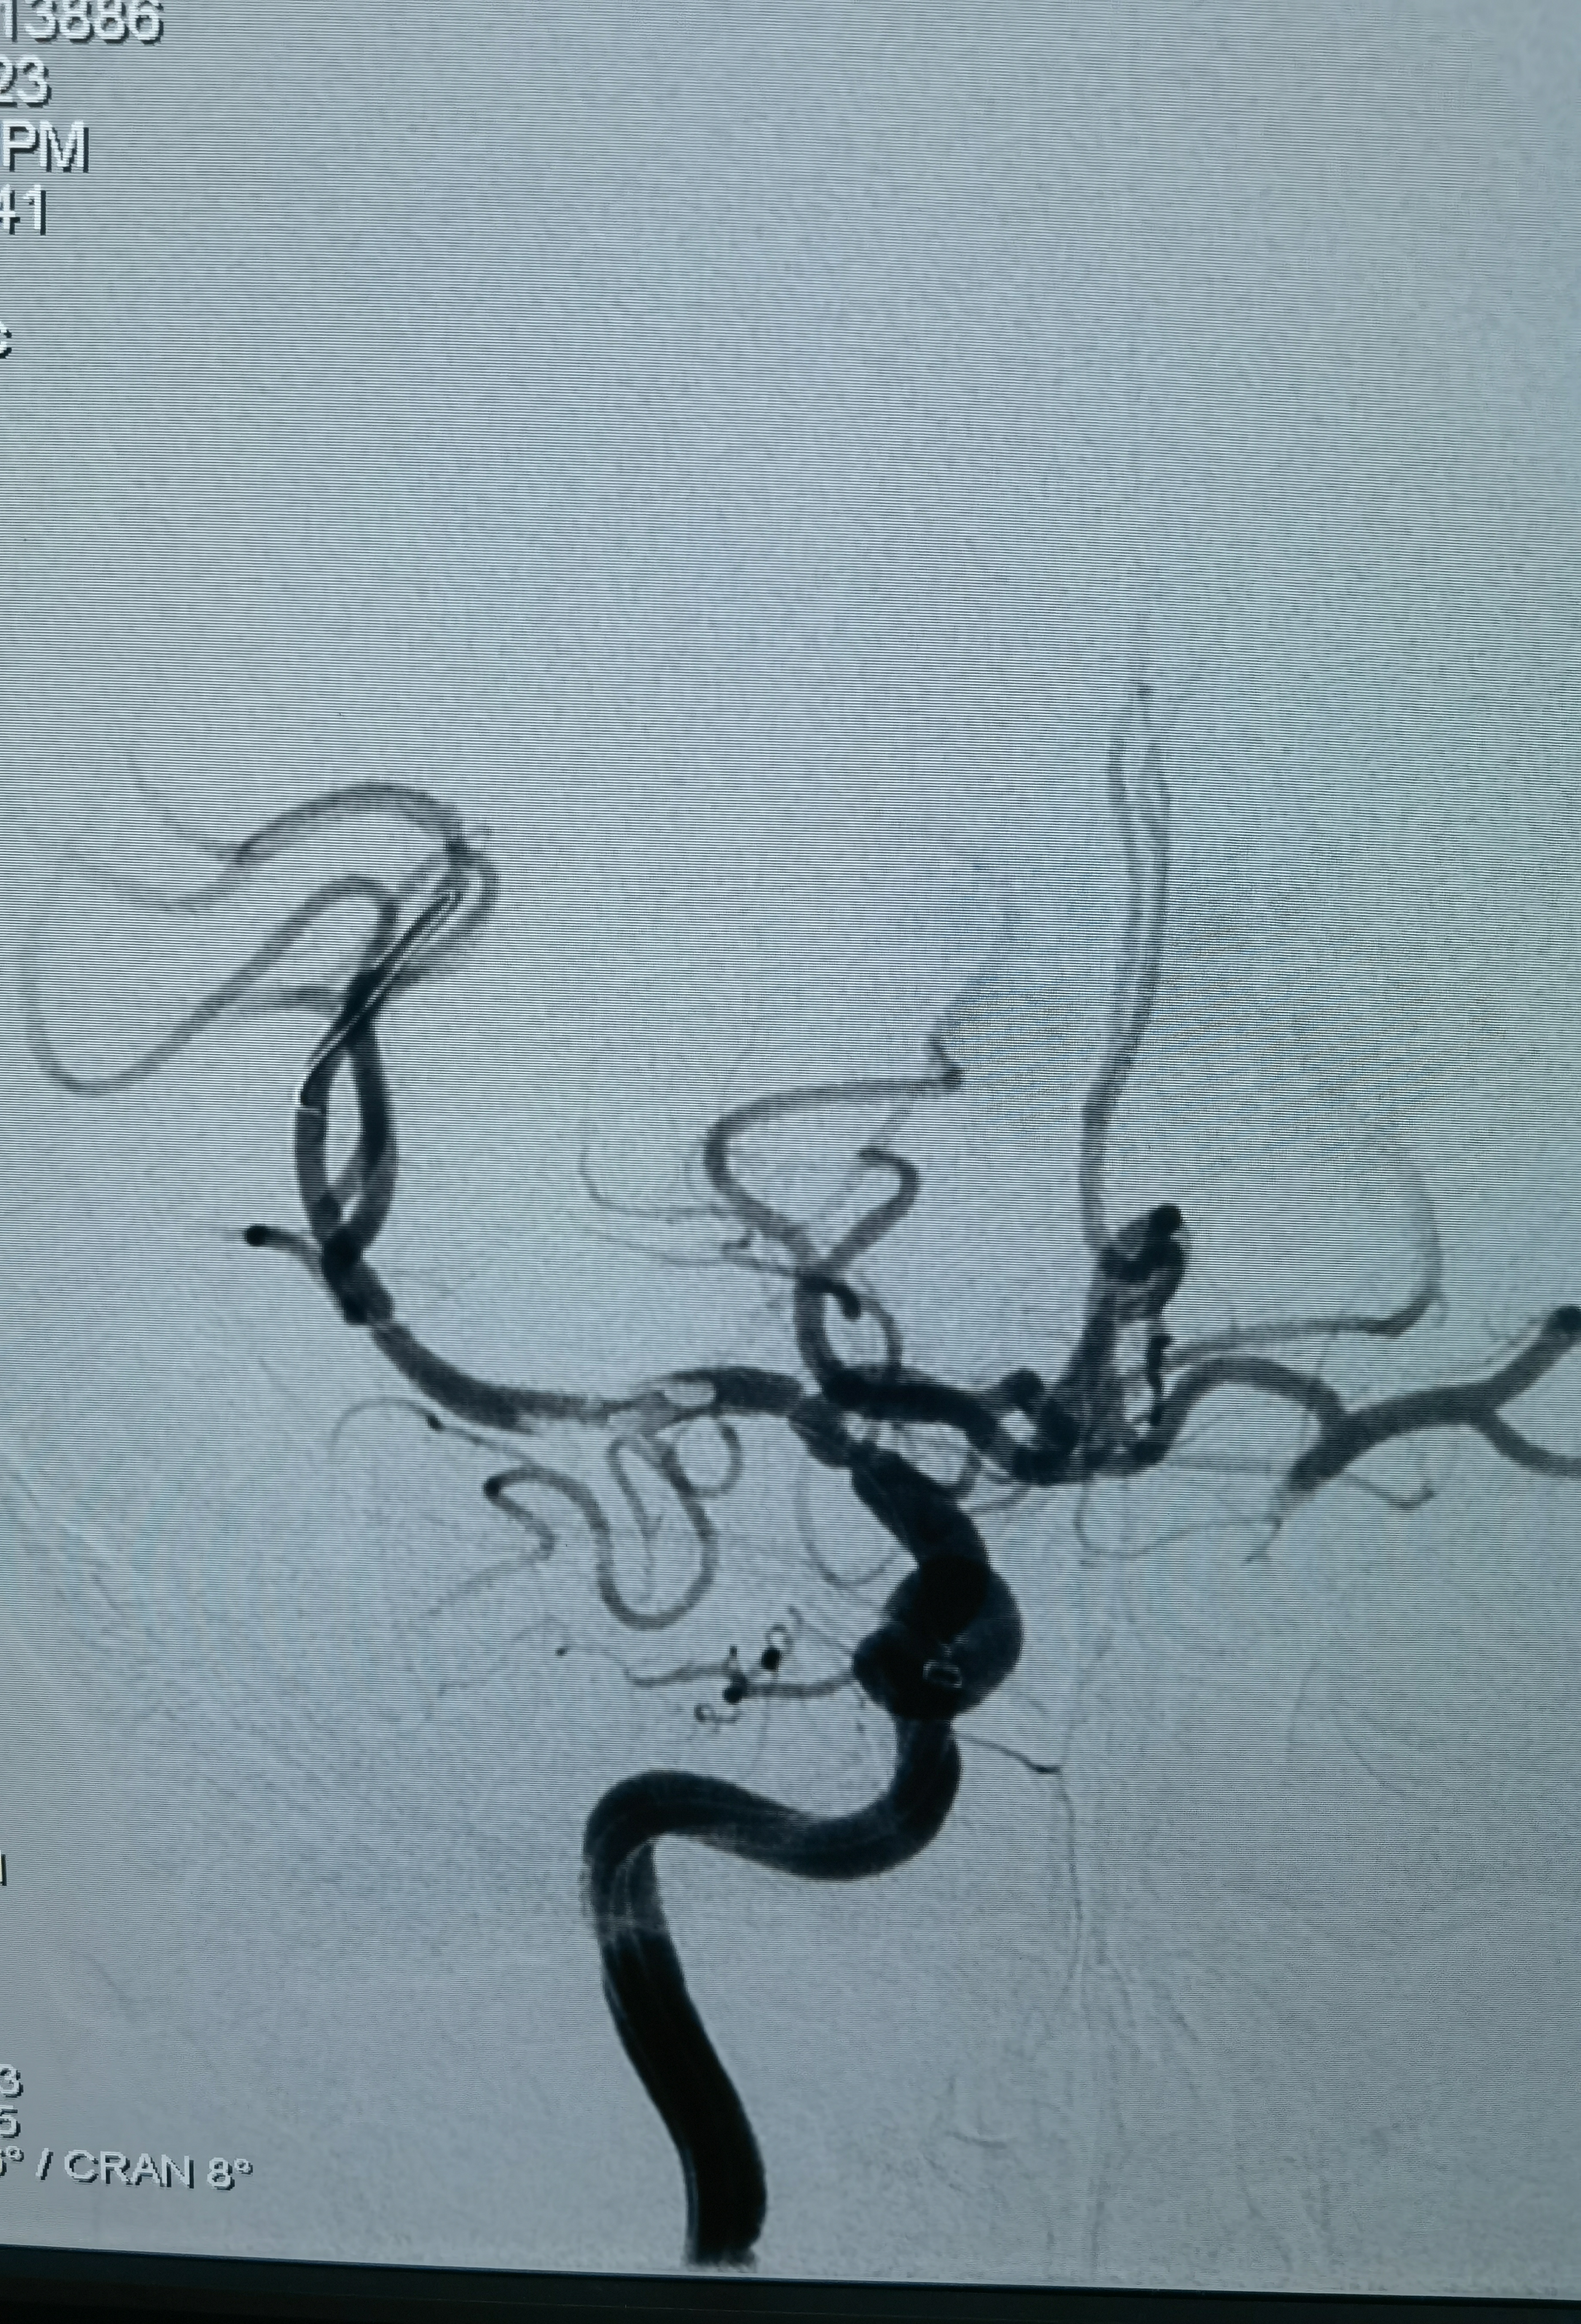

再上取栓支架,这是取栓支架打开造影,能看见支架压缩影,提示有狭窄!

支架取栓两次没通,不敢过多用支架拉了,上球囊扩张两次,大脑中水平段扩一次,远端扩一次!

扩完血流恢复,血管通了,但是大脑中动脉M1仍有血栓,似乎还有点夹层,动脉给了10ml替罗非斑,观十余分钟,M1血栓又增加了,血流也变差,怎么办?想支架成型,但是患者有大动脉炎,不贴支架血流维持不住,术中商量一下考虑患者年轻,还是要尽量让患者降低瘫痪的机率,遂决定植入药物涂层支架,就算动脉炎引起支架内闭塞也需要一定时间,患者大脑前有通过软膜支向大脑中供血区代偿,到时候慢性闭塞可能患者不会出现严重影响!